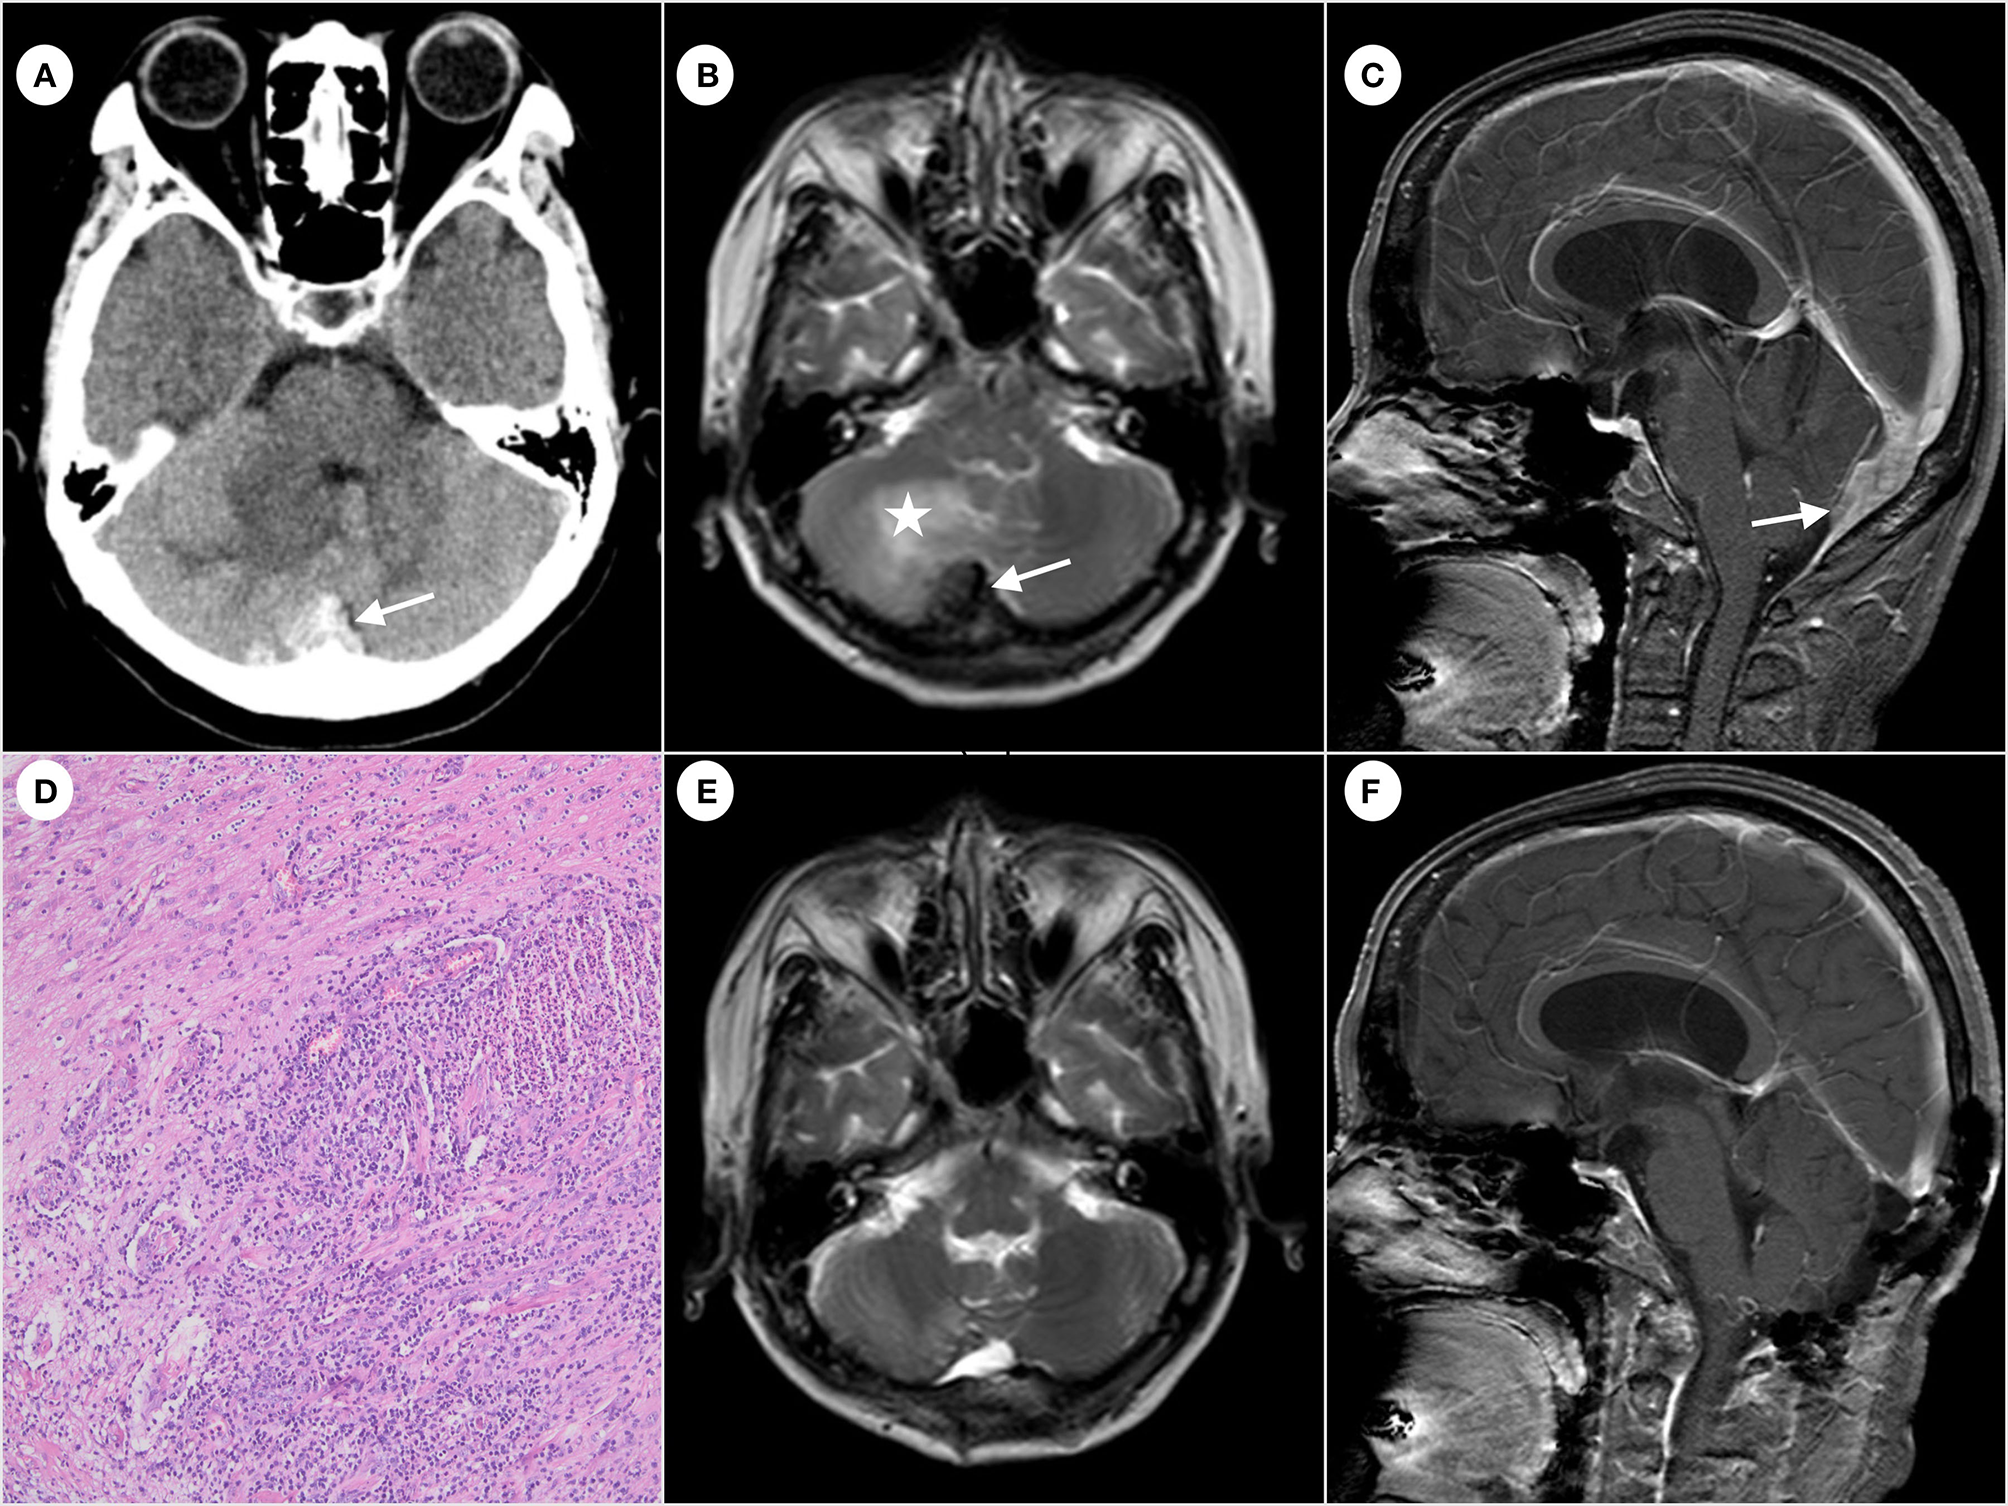

A 54 year-old woman was admitted to the Qilu Hospital of Shandong University for paroxysmal headache for 2 years that had worsened in the past 3 months without fever, nausea, and vomiting. The patient had no lymphadenopathy and denied exposure to fleas recently. The patient had normal muscle tone of limbs, negative pathological findings, normal results of routine blood tests, and negative tumor markers. The patient had no relevant past medical history, no medication history, and no travel history. In addition, the patient denied consuming undercooked meat. The CT scan showed an irregular high-density mass below the occipital plate, with patchy low-density areas in the right cerebellar hemisphere (Figure 1A), which the radiologist suspected to be a dural tumor and the neurosurgeon recommended performing MRI. The MRI scan showed that the lesion with a broad base was connected to the dura mater, with slightly shorter T1 and T2 signals (Figure 1B). The enhanced scan showed a significant enhancement and a dural tail sign (Figure 1C). The patchy area of no enhancement in the right cerebellar hemisphere was considered edema. The patient was diagnosed with atypical meningioma by radiologists and neurosurgeons before the operation. En bloc resection of the sinus junction area was performed, and then, the fascia lata of the left lower limb was used to repair the dura mater. While the lesion involving the venous sinus was not completely resected, the pathological examination showed granulation tissue and fibrosis with acute and chronic inflammation, granuloma, and central stellate micro-abscess (Figure 1D), which was suspected as the cat-scratch disease (CSD) by the pathologist. The paraffin-embedded tissue was sampled for a polymerase chain reaction (PCR) test to amplify the corresponding pathogen gene sequence, which was Bartonella henselae. Therefore, the diagnosis of cat-scratch disease was confirmed. A more detailed medical history showed that, although the patient had no contact history with cats or dogs recently, she was scratched by a dog more than 10 years ago. The patient then received oral rifampicin (450 mg once daily for 4 weeks) and compound sulfamethoxazole (960 mg two times daily for 2 weeks) as part of antibiotic therapy. The follow-up MRI (Figures 1E, F) showed that the residual lesions in the surgical area disappeared at 4 weeks after the operation. No special symptom was found after 6 months of follow-up.

Figure 1

Computed tomography of the brain showing irregular high-density mass (arrow) below the occipital plate (A). Hypointense (arrow) on T2-weighted magnetic resonance imaging and edema (star) observed near the right cerebellar hemisphere (B). The enhanced scan shows significant enhancement and a dural tail sign (arrow) (C). Formation of granuloma and central stellate microabscess. The image was acquired at 100× magnification (D). The follow-up MRI shows the disappearance of the residual lesion in the surgical area (E, F).